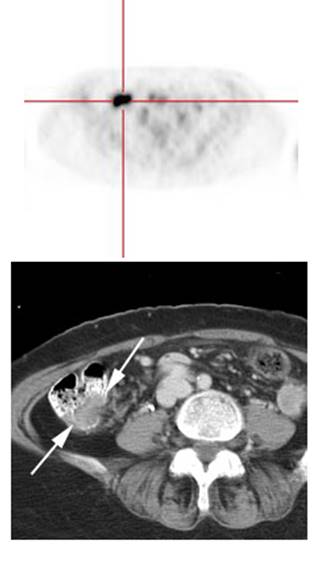

Figure 7 - Bladder cancer: Despite urinary excretion

of the radiotracer, this patients bladder cancer

(white arrows) is readily identified on the PET scan (black arrows). In

general, however, urinary excretion of FDG limits evaluation of urinary tract

malignancy